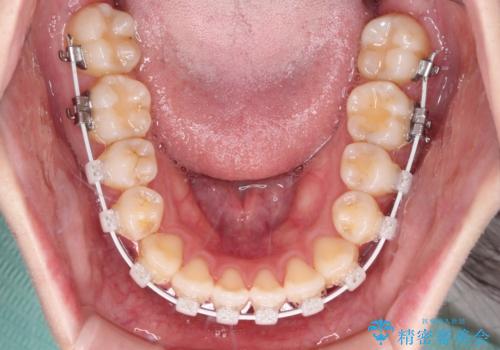

- 審美装置

上下前歯が非接触である開咬は、インビザラインによる治療がお勧めではありますが、しっかりと使う自信がないとのことで、ワイヤー装置にて治療を行うこととしました。

ワイヤー矯正での開咬改善には時間がかかります。

舌の突出癖改善のトレーニングをしっかりと行っていただき、上下前歯が接触する咬み合わせを達成することができました。